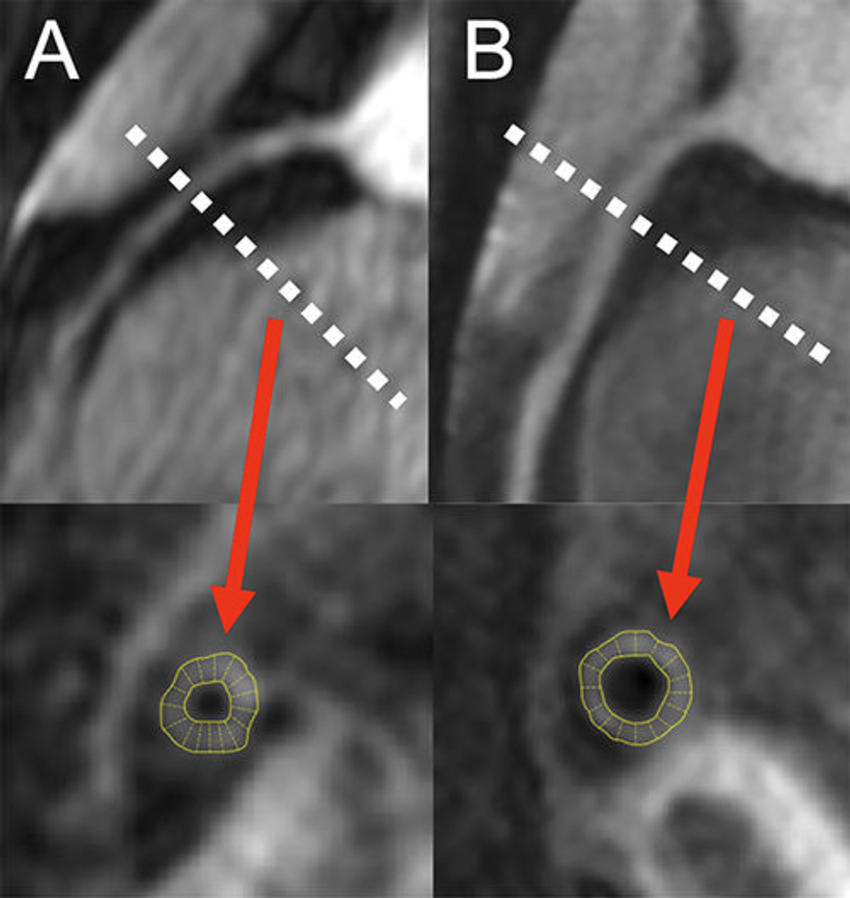

Figure 2. MR angiograms (top row) of the right coronary arteries in two persons living with HIV (PLWH) show location of cross-section (dotted lines) of coronary vessel wall image (bottom row) and the corresponding automatic wall thickness measurement. (A) Image from 50-year-old male PLWH with increased coronary vessel wall thickness of 1.5 mm and grade 1 diastolic dysfunction. (B) Image from 52-year-old male PLWH with coronary vessel wall thickness of 1.2 mm and normal diastolic function.